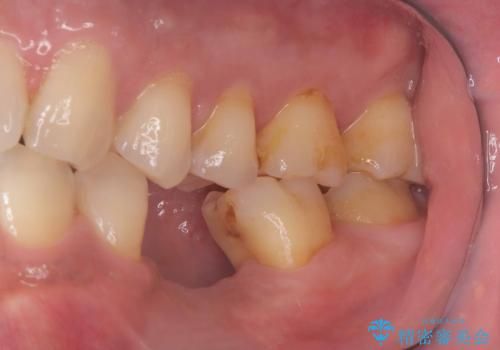

- 20年振りの来院で下顎左右5番にインプラント入れていた患者様です。

右下5番のインプラントは問題ありませんでしたが、左下5番のインプラントがインストール周囲炎に罹患している状態でした。

インプラントを抜去後、再びインプラントで治療を行いました。